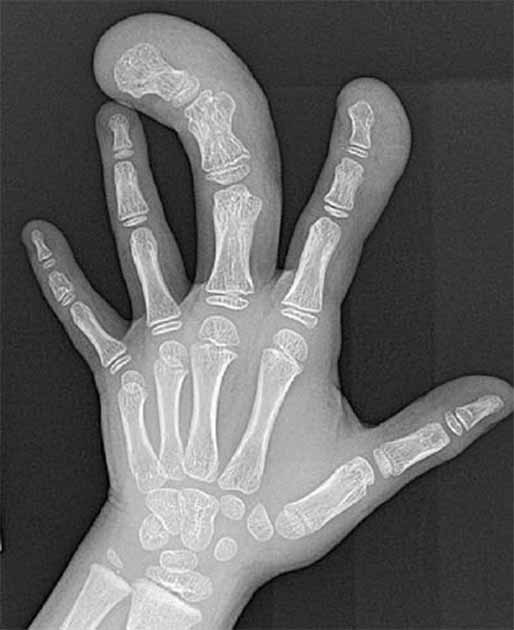

A radiograph of the left hand showing Macrodystrophia. (Dillman, J.R., Strouse, P.J. Macrodystrophia lipomatosa/Pediatr Radiol 40, 372 (2010))

Scientists have studied the pictures but were not able to draw any conclusion on the basis of images alone. They did however confirm that the mummified finger appeared authentic but rejected the possibility of a past race of giants. They investigated the possibility of whether the finger may be related to makrodactylie (or Proteus syndrome or gigantism). This condition involves the excessive growth of the toes or fingers of the patient. This theory was subsequently discounted as the relic has normal proportions of thickness and size of the nail in relation to the length of the finger. In Makrodactylie this ratio is absent and the bone will be longer than normal.